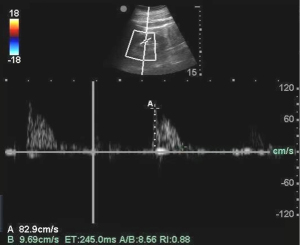

For SMARI measurement (9), patients were placed in a supine position (7). The probe was positioned along the longitudinal section of the abdominal aorta to visualize the long axis of the superior mesenteric artery. Measurements were taken 1.0–2.0 cm distal to the origin of the artery. The pulsed wave Doppler was used to obtain the blood flow velocity spectrum, with an angle of 25°–45° between the bloodstream and the sound beam. The waveform was recorded for three cardiac cycles, and the mean value was calculated (Figure 1).